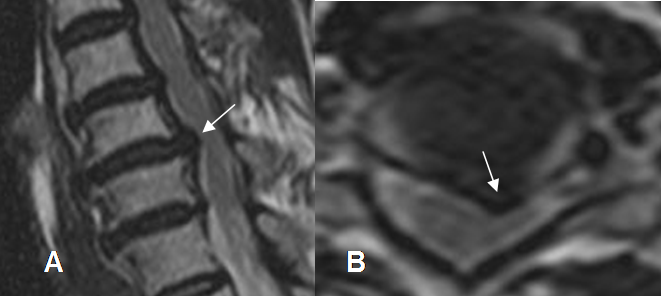

Fig 101. Hernia paramediana.

A: RM sagital y B: RM axial en T2. Prominencia asimétrica paramediana izquierda, que corresponde a hernia. Adicionalmente hay canal estrecho asociado.

Fig 102. Hernia foraminal.

A y B: TAC axial. Obliteración de la grasa foraminal, con imágenes con densidad de tejido blando, que corresponden a hernias.

Fig 103. Hernia foraminal.

A: RM axial en T2 y B: RM axial en T1. Obliteración de la grasa foraminal, con imágenes con densidad de tejido blando, que corresponden a hernias.